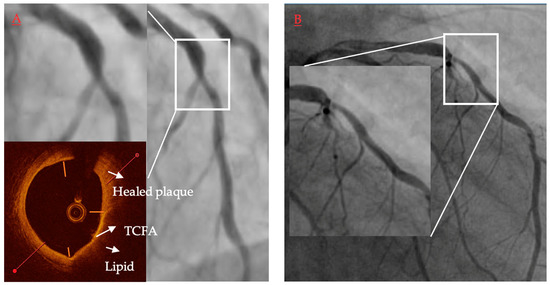

OCT with high accuracy describes the plaque composition, distinguishing between lipid-rich, fibrotic and calcified tissues (Figure 4). Lipid-rich plaques characterize a high signal attenuation in the vessel wall without clearly identified borders. A calcified lesion characterizes a high signal drop with clear borders. Fibrotic lesion characterizes a moderate signal attenuation with visible media behind the plaque [51].

Figure 4.

Representative images of optical coherence tomography findings in patients with acute myocardial infarction. Lipid plaque is characterized as signa poor regions (asterisk) with overlying signal-rich bands (A). Thin-cap fibroatheroma is defined as a lipid plaque occupying more than >90° in circumference and with fibrous cap thickness (arrows) less than a set threshold (usually 65 μm or 80 μm) (B). Plaque rupture is defined as disruption of fibrous cap (arrows) with visible cavity within the plaque ((C) asterisk). Red thrombus is described as highly backscattering structure with high attenuation ((D) asterisk), whereas white thrombus is less backscattering and has lower attenuation ((D,E) #). Erosion is described as presence of attached thrombus (usually white; #) overlying an intact and visualized plaque (E). Calcification protruding to the lumen is described as calcific nodule ((F) asterisk).

Furthermore, it enables the measurement of the thickness of the fibrous cap covering the lipid pool and thus detects thin fibrous cap atheroma (TCFA). The globally accepted definition of TCFA is the lipid-rich lesion that extends to more than 90 degrees in the vessel circumference, covered with a fibrous cap less than 65 µm thick [38]. The autopsy study presented that lipid-rich lesions with fibrous cap less than 54 µm were mostly responsible for plaque rupture and sudden cardiac deaths events [5]. For OCT, the TCFA thickness threshold is 65 µm, concerning OCT resolution, which is around 10 µm. The downside of the OCT analysis is that it relies on the observers’ experience, and sometimes TCFA might be mistaken with massive calcification within the vessel, and with artifacts, such as signal drop [52]. OCT also enables the detection of other vulnerable plaque traits such as macrophages infiltration as bright spots scattered within the lipid-rich pools, as well as neovascularization [53,54].

In addition to the TCFA identification, the OCT is enabled to identify plaque erosion, which is a cause of the myocardial infarction in about 25–40% of all cases. Plaque erosion is defined as endothelial denudation [55]. Since the endothelial thickness (5 µm) is below the OCT resolution, Nir does not visualize it directly. However, a visible thrombotic mass attached to the vessel wall, in absence of a visible fibrotic cap rupture, is suggestive of plaque erosion. Another high-risk risk trait of atheroma detectable by OCT is calcification nodule. It is a calcification spot that sticks sharply to the lumen and exposes the vessel wall for intravessel thrombosis [55]. Further, OCT with its high resolution allows for the categorization of calcification in even more detail in patients with ACS: superficial calcific sheet, eruptive calcified nodules and calcified protrusion, with the first one being most frequent and being associated with the greatest postintervention myocardial damage [10].

OCT high-resolution images reflect the history of plaque formation. OCT easily enables the identification of plaque rupture, which is presented as a disrupted cap covering the lipid pool. It also detects the silent consequence of the plaque rupture, which is the healed plaque (honey-like structure with the signal shadowing within the plaque) [56]. Importantly, healed plaques are a quite frequent finding and may be associated with panvascular vulnerability. Russo et al., in a study comprising 163 patients with stable angina, found that healed culprit plaques in coronary arteries were present in more than half of the patients (53.4%) [4]. What is more, patients with healed culprit plaques showed more multivessel disease and had more features of plaque vulnerability. Similar results were found in ACS patients where over one quarter of them had healed plaques in culprit lesions [57]. Finally, Usui et al. showed that the presence of untreated healed plaques was positively correlated with non-culprit lesion related MACE [58].